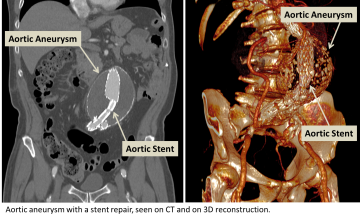

Endovascular stent grafting (EVAR, or endovascular aneurysm repair)

Endovascular stent grafting is a procedure that is performed to treat aneurysm or and dissection. A stent graft is an expandable vascular conduit which is placed into the diseased segment of vessel thereby reinforcing the vessel wall and reducing the potential of rupture or progression of disease.

- The procedure is performed by using a need to access a vessel in the arm or leg and placing wire into the vessel. The wire is navigated into the aneurysmal or dissected vessel using a fluroscope (x-ray machine) to guide the navigation.

- Once the wire is properly placed, an appropriate stent graft is selected based on many factors including the size of the vessel, the types of branches that come from the diseased vessel, and the type of aneursym or dissection being treated. The collapsed stent graft is fed into the target vessel using the wire and fluoroscope as a guide.

- Once the stent graft is appropriately positioned, a balloon is placed over the wire and into the center to the collapsed stent and used to expand the stent to seat it against the vessel wall.

- Contrast may be injected into the vessel to test the fit and seating of the stent graft. Once a satisfactory placement has been made, the wire and balloon are removed from the body and the puncture made in the arm or leg is sealed. The patient is then taken to the recovery area for post-procedural observation.